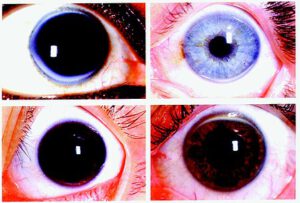

Conjunctivitis

Cheatsheets

1

Mnemonics

0

Images

1

Picmonic

0